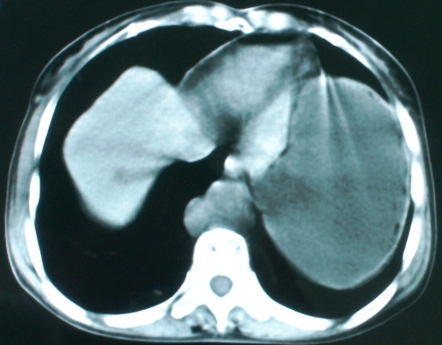

以下是引用zsl6918在2008-11-4 19:14:00的发言:[br]多发转移性改变,子宫改变不除外为原发灶